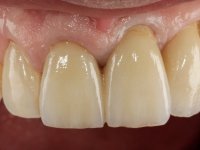

66-year-old male patient, non-smoker. It featured a 5-member metal-ceramic bridge with extreme mobility. Teeth 11 and 21 had infiltrated cervical margins. Both arches showed root exposure with signs of cervical abrasion. Composite resin “slots” were visible on the buccal surfaces of some mandibular teeth compatible with an orthodontic treatment with aligners that the patient was undergoing. After the imaging examination, it was found that the bridge's distal support, tooth 24, was irretrievably lost. The mesial pillars 11 and 21 had endodontic treatment and intraradicular posts. Teeth 25 and 26 also had endodontic treatment and extensive restorations in composite resin. In the lower jaw, two bridges were visible. In the third quadrant a 4-element bridge supported on tooth 35 and on 2 implants placed in the location of teeth 36 and 37. In the fourth quadrant a 3-element bridge supported on tooth 45 and an implant placed in the location of tooth 46. The patient presented a thick gingival phenotype and very good oral hygiene.

A temporary acrylic bridge made in the laboratory with 7 elements was made, with teeth 11,21, 25 and 26 as pillars. The old bridge was removed and tooth 24 was extracted. The provisional bridge after relining was cemented in the mouth. Two implants were placed in the teeth 22 and 24 and 3 months after this intervention an impression was made to make a temporary bridge screwed over the implants and cemented to the teeth. The bridge was placed in the mouth and teeth 25 and 26 were extracted. 3 months later, surgery was performed to fill the maxillary sinus and 6 months later the implant was placed in the location of tooth 26. After osseointegration of this implant, the final impression was made for the final work. The bridge over the implants was permanently screwed on and the bridge over the teeth was cemented with resin-reinforced glass ionomer cement.